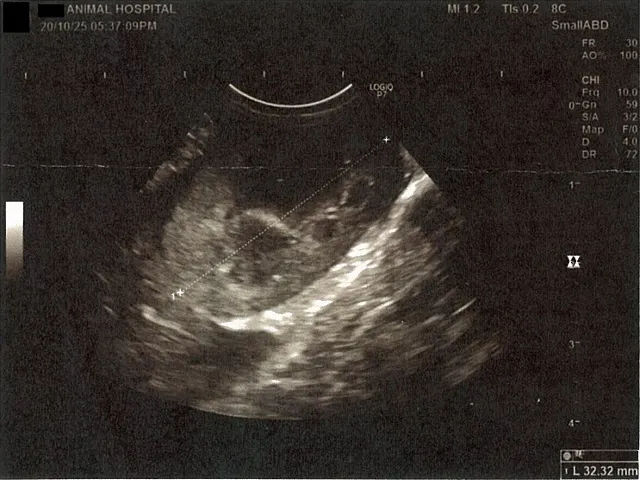

左腎臓周りに腹水が確認できるエコー写真

心臓のみ腹水が確認できないエコー写真